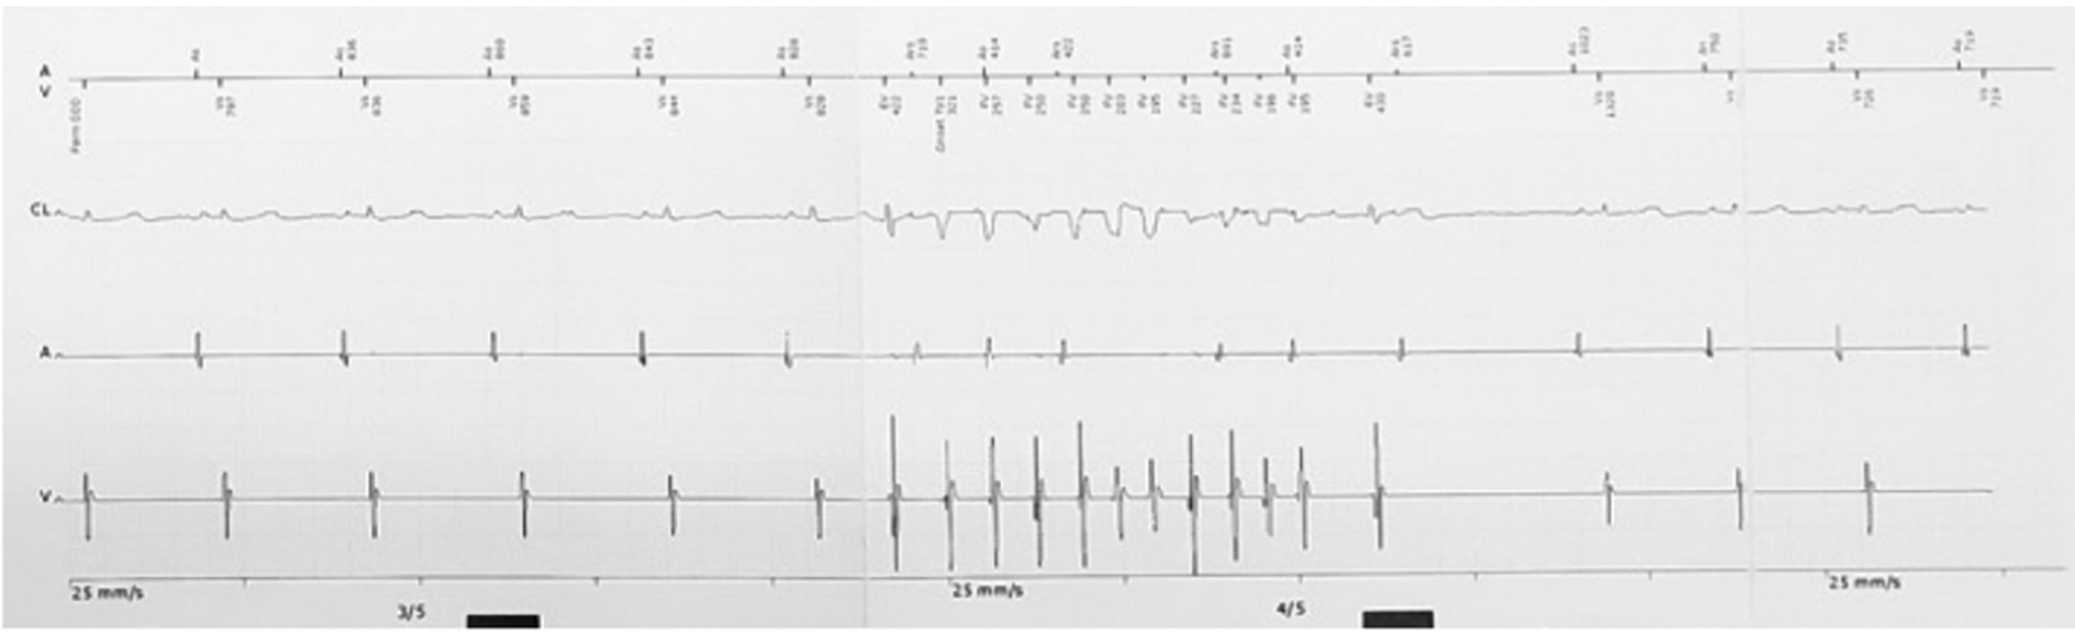

然而,故事并沒有這么簡單,入院后室早才一步步顯露出它的真面目。這次發作的室早與入院時明顯不同,聯律間期縮短至300ms,出現在T波頂峰,室早后誘發了尖端扭轉型室速(TdP),室速發作時患者同時出現了暈厥發作。此后,患者又出現了多次TdP發作,且發作時間越來越長,最終演變成室顫,體外除顫后才恢復正常竇律。

圖3 短聯律間期室早誘發尖端扭轉型室速